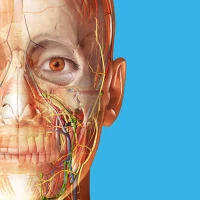

Using our cutting-edge 3D model, which is one of the most detailed in the world, ANATOMYKA allows you to get up close with human anatomy in all its breathtaking complexity on more than 13,000 anatomical structures with more than 500 pages of medical descriptions. Now in English, Spanish, Italian, Polish, Russian, Czech, Slovak and Hungarian localization.

Color-coded organs allow users to view high-resolution anatomical structures supplemented by informative descriptions from a comprehensive textbook ‘Memorix Anatomy’. These are arranged into a proper anatomical hierarchy, meaning learning is structured and easy to understand.

Choose from different themes for a better visual experience, including classic atlas, dark atlas, dark space and cartoon style.

Set your own color for organs, structures or systems for more effective memorizing.

Create labels and pin them to different parts of the body. Labels automatically highlight the name and color of the organ and are great for creating anatomical posters.